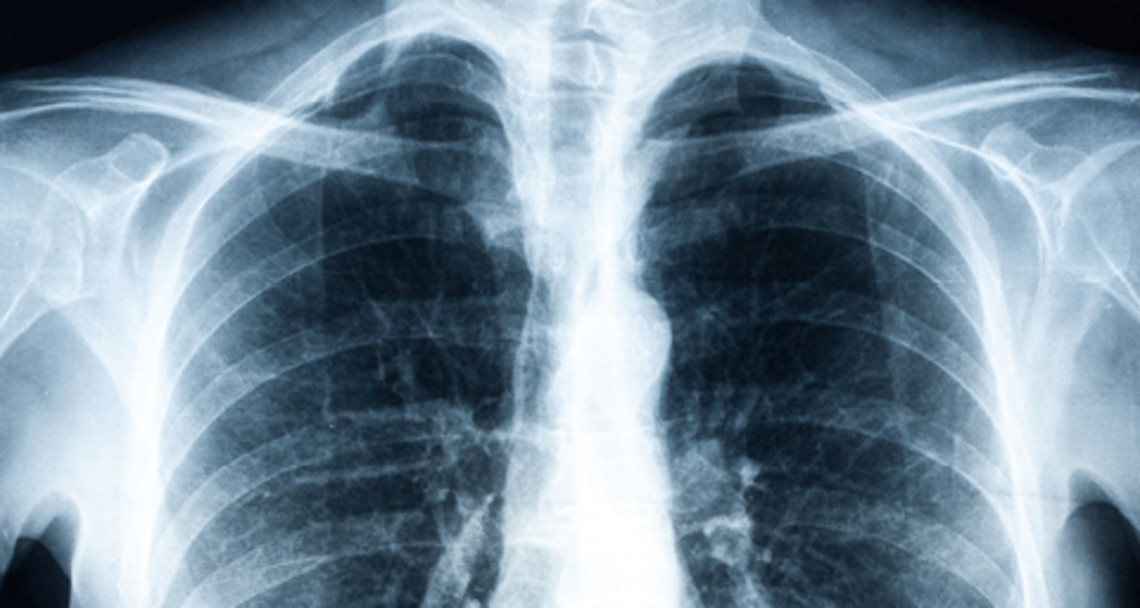

Le sigle BPCO signifie bronchopneumopathie chronique obstructive. Il s'agit d'un terme générique désignant différentes affections dont les symptômes sont similaires. Les patients atteints ressentent de l'essoufflement et souffrent d’une toux chronique. Ils ont tendance à avoir des performances physiques limitées et des expectorations fréquentes. Le diagnostic de la BPCO comporte quatre degrés différents, allant de 1 (léger) à 4 (grave). Les fumeurs doivent être attentifs aux signaux d'alarme car cette population est particulièrement touchée par la BPCO. Si l’on souffre d'une toux persistante ou de difficultés respiratoires, il est conseillé de consulter un médecin généraliste qui oriente généralement le patient vers un pneumologue.

Le pneumologue commence par établir un compte rendu détaillé des antécédents (gravité des symptômes, habitudes tabagiques, contact avec des substances nocives, etc). Il va également ausculter le patient puis tester sa capacité pulmonaire à l’aide d’un appareil de mesure, lors d’un test d’effort. Il pourra alors identifier si les symptômes sont associés à une BPCO. Une fois le diagnostic posé, il est important pour le patient d’être soutenu, aussi bien par son entourage que par son médecin.

Lorsque le patient consulte pour la première fois, il n’est pas rare que sa vie soit déjà impactée par les différents symptômes de la BPCO. Les signes typiques de la BPCO sont bien trop souvent minimisés par les personnes concernées mais l’un d’entre eux est une sensation d'oppression quasi-permanente dans la poitrine. Sans être handicapant au départ, cette sensation peut vite évoluer et diminuer fortement les capacités physiques du patient. À un stade sévère, même les activités quotidiennes les plus simples, comme s'habiller ou encore monter quelques marches d’escalier, peuvent laisser le patient à bout de souffle.